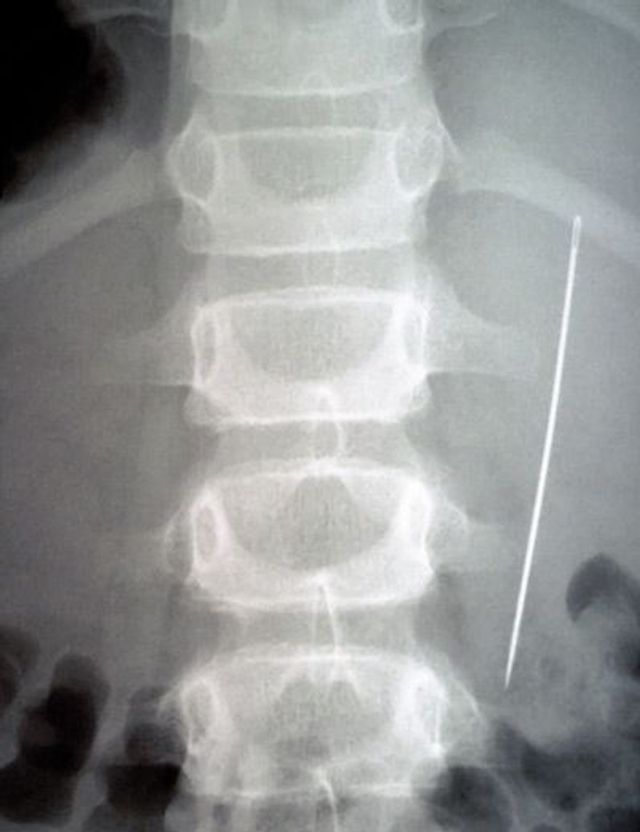

Sie entlarven von außen nicht erkennbare Verletzungen, somit auch Spuren von Folter. Eine gerichtsmedizinische Untersuchung macht Frakturen, eingeführte Fremdkörper, Nadeln sichtbar. Die Aufnahmen ermöglichen eine Plausibilitätsprüfung. Stimmen die Schilderungen des Opfers mit dem Verletzungsmuster überein? Stimmt das Alter der Verletzung überein mit dem Zeitraum, den die Person für die erfahrene Folter angibt? Entspricht die Foltermethode dem, was für die angegebene Region und die verantwortliche Organisation, Militär oder Miliz, bekannt ist?

Ja, ebenso bei Asylverfahren. Für die Opfer ist es ein weiteres Argument, wenn ein Radiologe ihre Aussagen bestätigt. Behörden haben ja den Hang, nicht nachweisbare Vorgänge als »unwahr« abzuschließen. Die Röntgendiagnostik ist jedoch kein massentaugliches Element. Meist reichen einfache Mittel, um ein Folteropfer zu erkennen: Viele erbrechen zum Beispiel vor Angst, wenn ein Mensch in Uniform den Raum betritt.